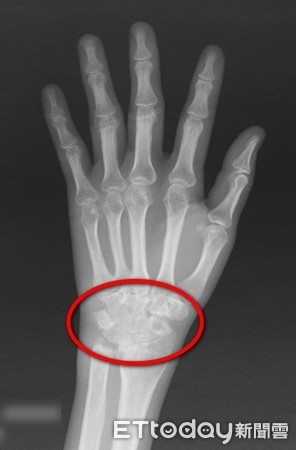

▲影像檢查顯示許小姐手腕肌腱斷裂。(圖/台北慈濟醫院提供)

31歲的許小姐是位鋼琴老師,有類風濕性關節炎病史,近2年工作繁忙,無法定期回診,加上密集教學,手腕開始發炎疼痛,中指、無名指、小指都無法伸直抬起,更罔論彈琴。赴醫院檢查才發現,她右手三條肌腱斷裂,空隙長達6公分,因無法直接修補,只能取大體老師捐贈的多條肌腱韌帶移植,重建回縮肌腱,經過2個月癒合及復健,終於能重新彈琴。